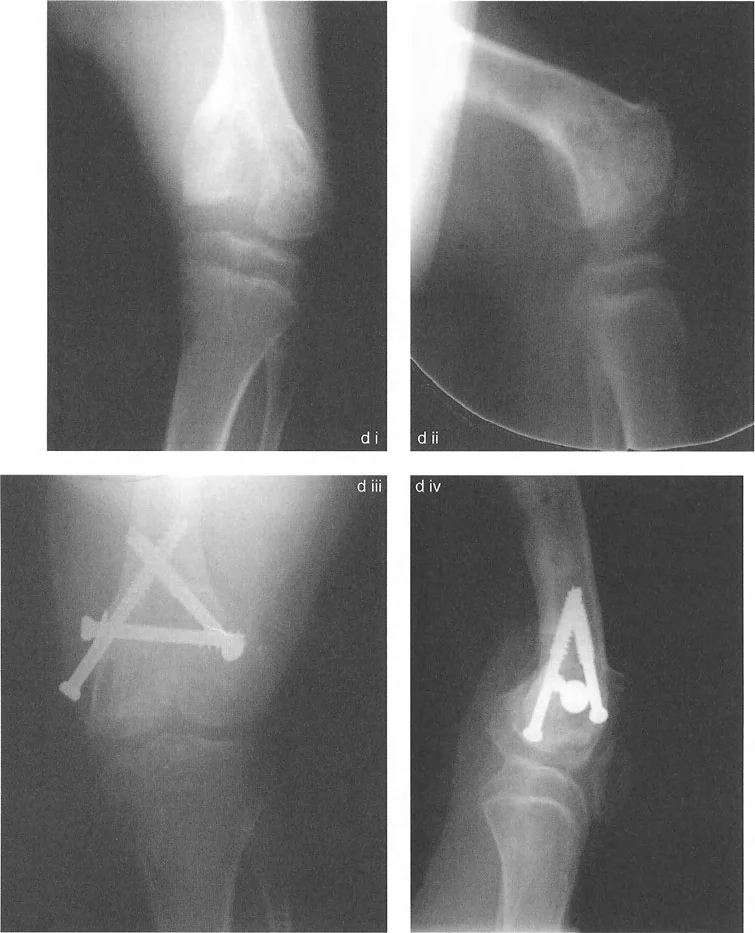

- مرض بلونت (تقوس الساق): في مرض بلونت الشديد لدى الرضع أو المراهقين، تتميز الحالة بانخفاض شديد وميل إنسي للهضبة الظنبوبية الإنسية. إذا رسمت الخطين، فإن خطي الهضبة الإنسية والوحشية يكونان بزاوية حادة بالنسبة لبعضهما البعض، ويتقاطعان بالقرب من مركز الركبة. وهذا يخلق دفعاً تقوسياً شديداً أثناء المشي.

- متلازمة إليس-فان كريفيلد (خلل التنسج الغضروفي الجلدي): تؤدي هذه الحالة الوراثية إلى انخفاض "متدرج" مميز في الهضبة الظنبوبية الوحشية. ومن المثير للاهتمام أن خطي الهضبة غالباً ما يظلان متوازيين لبعضهما البعض، لكنهما يقعان على مستويات أفقية مختلفة تماماً، مما يخلق فرقاً كبيراً في المستوى وتشوهًا شديدًا في وضعية الركبة (valgus).

* توقف النمو الإنتاني: عدوى في مرحلة الطفولة (التهاب العظم والنقي / التهاب المفاصل الإنتاني) تدمر صفيحة النمو لقمة الفخذ الوحشية مما يؤدي إلى لقمة وحشية ناقصة التنسج، سيئة التوجيه، و "متدرجة" مقارنة بالجانب الإنسي السليم الذي ينمو.

* التئام العظم بعد الصدمة بشكل خاطئ: كسر سالتر-هاريس لدى الأطفال أو كسر بين اللقمتين لدى البالغين يلتئم بشكل سيء ينتج عنه درجة مميزة و/أو سوء توجيه للقم.

* توقف النمو المركزي (تشوه ذيل السمكة): توقف النمو في المركز الدقيق لصفيحة النمو الفخذية البعيدة يتسبب في سوء توجيه اللقمتين وانحدارهما نحو المنتصف، مما يخلق مظهراً كلاسيكياً "لذيل السمكة" على صور الأشعة السينية الأمامية الخلفية.

التأثير الجراحي: بسبب هذا التسامح الهندسي، يمكن غالباً إعادة محاذاة سوء المحاذاة الناتج عن إزاحة لقمة الفخذ الأحادية أو سوء توجيهها باستخدام قطع عظم الفخذ فوق اللقمي خارج المفصل. لا تحتاج دائماً إلى تقسيم اللقم وإجراء عملية داخل المفصل عالية المخاطر. على النقيض من ذلك، فإن عدم الاستقرار الشديد الناتج عن درجات عظم الساق يتطلب دائماً تقريباً قطع عظم حقيقي داخل المفصل (رفع الهضبة) بدلاً من مجرد تصحيح في الميتافيزيس، لمنع التدمير السريع للمفصل.